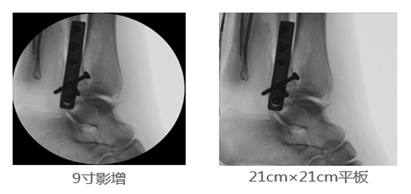

2、成像視野:在圖像尺寸方面, 9英寸平板與9英寸影增相比,平板探測器成像為“方形”,較同尺寸的影像增強器的“圓形”成像而言,有效視野面積擴大了22%,使醫生的觀察視野更加開闊,極大的提高了手術的效率,同時提高了各種手術的安全性。